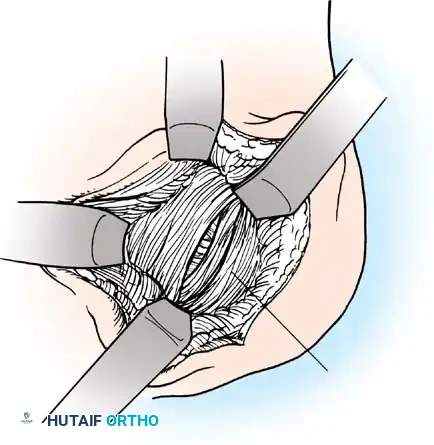

Subscapularis Management

Exposure of the anterior capsule requires navigating the subscapularis muscle. Historically, a vertical tenotomy was performed; however, modern techniques favor a subscapularis split or a peel to preserve the integrity of the muscle belly and its tendinous insertion.

- The Split: A horizontal split is made in the subscapularis at the junction of its middle and inferior thirds, extending from the lesser tuberosity medially.

- Separation: The subscapularis is carefully elevated off the underlying anterior joint capsule. This plane can be scarred in revision cases, requiring meticulous sharp dissection to avoid inadvertent capsulotomy.

Capsulotomy and Joint Inspection

A vertical or T-shaped capsulotomy is performed based on the degree of capsular laxity and the planned shift.

- For a standard Bankart repair with an inferior capsular shift, a vertical incision is made 1 cm medial to the humeral articular margin. A horizontal limb can be added to create superior and inferior capsular flaps.

- Tagging sutures are placed in the capsular flaps for traction.

- A Fukuda retractor is placed within the joint to retract the humeral head laterally and posteriorly, exposing the anterior glenoid rim and labrum.